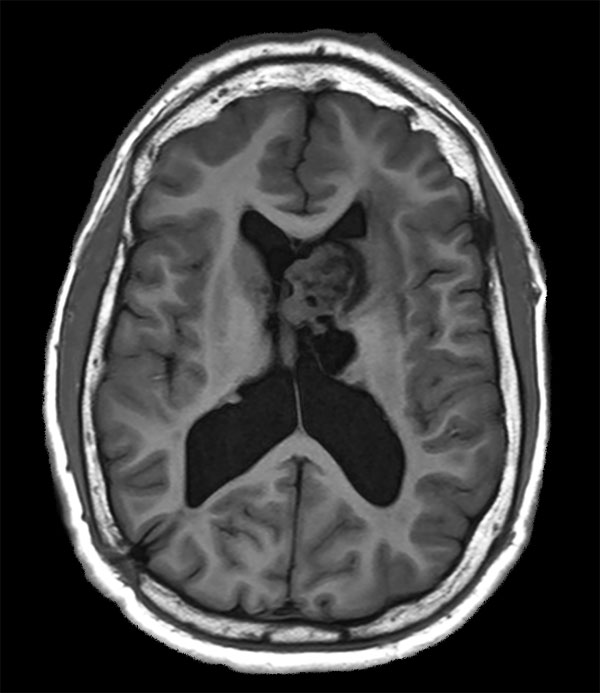

Axial T1W IR TSE